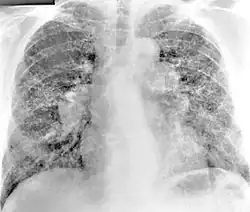

Projev chronické berylliózy na plicích

Beryllium a především jeho soli jsou ze zdravotního hlediska velmi rizikové. Jsou jak přímo toxické, tak potenciálně karcinogenní, tedy schopné vyvolat rakovinu nebo alespoň zvýšit riziko jejího výskytu. Vysoká toxicita beryllia je nejspíše způsobena jeho schopností vytěsnit hořčík z enzymů[5].

Při dlouhodobém vdechování zvýšeného množství aerosolu a mikroskopických částeček s obsahem beryllia vzniká plicní choroba – chronická beryllióza. Je známa již z první poloviny 20. století a prokazatelně postihuje pracovníky, kteří byli dlouhodobě vystaveni pobytu v prostředí s vysokým obsahem prachových částic na bázi beryllia. Jisté procento případů berylliózy obvykle bohužel přerůstá v plicní rakovinu.